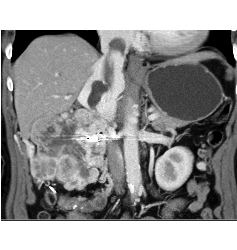

Peripheral Vascular Disease (PVD) Runoff